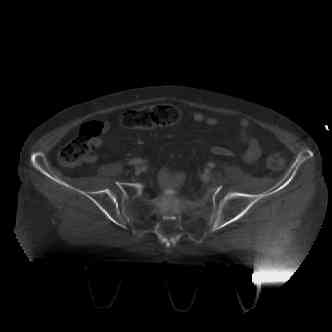

attached are images of a 70 year old female after peds versus car. her own car ran her over.

injuries are limited to the pelvis. left rami open and visible in a 10cm vertical laceration just lateral to left labia majora. wound is grossly clean. no vaginal and no urinary issues. CT scan shows widening of both SI joints anteriorly but I think this is vertically stable pattern.

attached are several CT cuts. please let me know if you need more. the CT is pre-pelvic ex-fix placement.